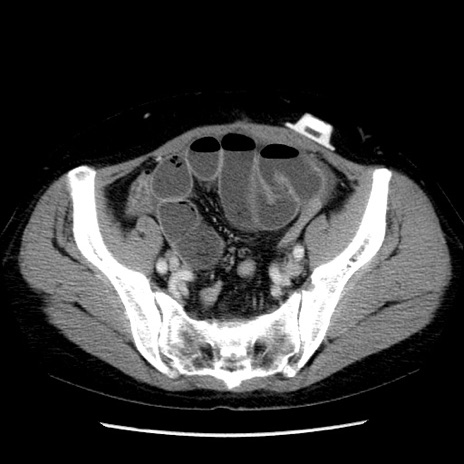

症例6(横断像)

【症例】50歳代女性

【主訴】下腹部痛

【現病歴】本日朝より下痢2回あり。 昼食を食べた後、嘔吐3回、下腹部痛認め、症状軽快せず、当院救急搬送。

最終食事:本日昼(生ものなし)。 昨日の夜、刺身を食ぺたとのこと。周囲に同様の症状の者なし。普段、排便は毎日あるとのこと。

【既往歴】卵巣癌術後(8年前に当院で卵巣摘出)

【身体所見】 意識清明、腹部:平坦、腸蠕動音→、やや硬、下腹部自発痛・圧痛あり、反跳痛あり、筋性防御なし。

【データ】WBC 16000、CRP 0.01